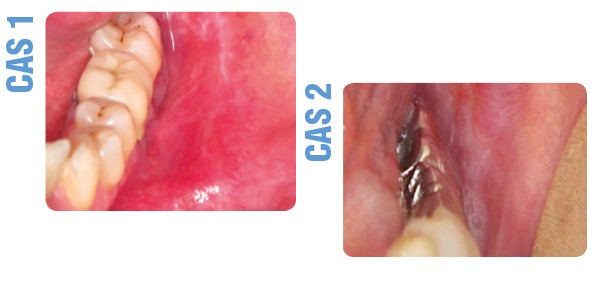

Il révélait une lésion érythémato-érosive d’environ 2 cm dans son grand axe, associée à un réseau kératosique. La lésion siégeait en regard des prémolaires et molaires, la 36 étant recouverte d’une couronne céramique. L’examen du reste de la cavité buccale révélait des lésions kératosiques en réseau de la joue droite et des plaques kératosiques de la face dorsale de la langue. Les aires ganglionnaires cervico-faciales étaient libres.